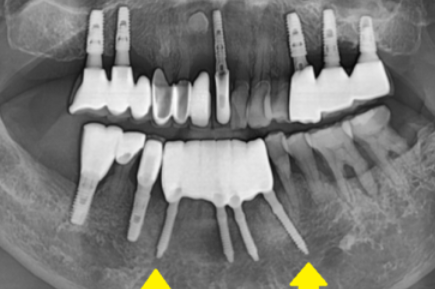

정확한 검사를 시행해 보니

더욱더 확실해졌습니다.

까맣게 된 것이 다 뼈가 녹은 부위입니다.

치아가 손으로 밀어도 흔들린다는 것은

잡고 있는 뼈가 거의 없다는 것

역시나 사진에서 잇몸뼈가 녹아내린 것이 확인

그냥 손으로 잡아 뽑아도 뽑힐 정도였습니다.